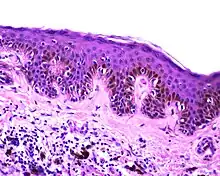

| Dysplastic nevus | Usually a compound nevus with cellular and architectural dysplasia. Like typical moles, dysplastic nevi can be flat or raised. While they vary in size, dysplastic nevi are typically larger than normal moles and tend to have irregular borders and irregular coloration. Hence, they resemble melanoma, appear worrisome, and are often removed to clarify the diagnosis. Dysplastic nevi are markers of risk when they are numerous, such as in people with dysplastic nevus syndrome. According to the National Institute of Health (NIH), doctors believe that, when part of a series or syndrome of multiple moles, dysplastic nevi are more likely than ordinary moles to develop into the most virulent type of skin cancer called melanoma.[19] | ![]() In this case, the central portion is a complex papule, and the periphery is macular, irregular, indistinct and slightly pink. |

Characteristic rete ridge bridging, shouldering, and lamellar fibrosis. H&E stain. |